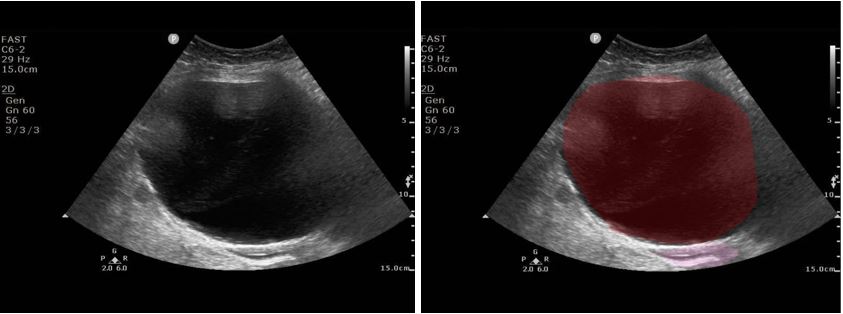

Her pain improved, and she was discharged home. She returned 24 hours later with 9/10 abdominal pain. On arrival, the patient received 4mg of morphine, 4mg of Zofran, and 1L of normal saline. Due to her persistent severe pain, she had an abdominal CT that was notable for a 10cm cystic lesion adjacent to the bladder and uterus (Figure 2). The radiologist noted the bladder was decompressed by the cyst. She was taken to the OR with gynecology and found to have a very large, edematous, and hemorrhagic right fallopian tube with hydrosalpinx. She was found to have a normal left fallopian tube and well-perfused bilateral ovaries. Her right fallopian tube was removed.

Figure 2: CT Abdomen and Pelvis. Red: Hemorrhagic Hydrosalpinx; Pink: Uterus; Yellow: Bladder